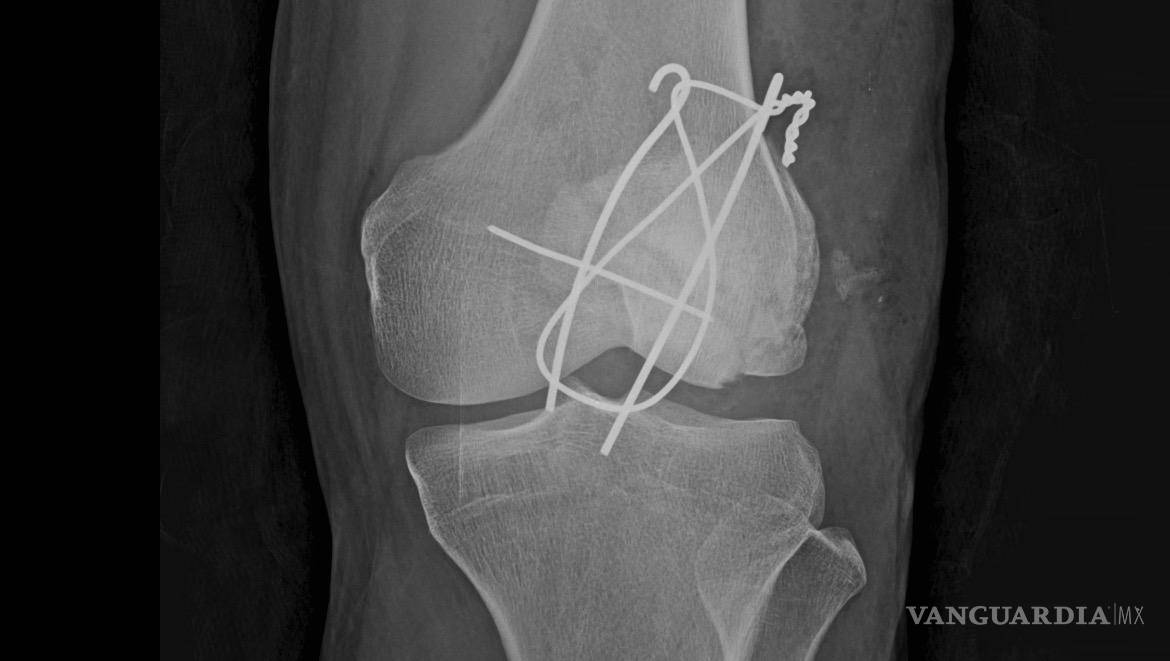

Taft afirmó que la ayuda de emergencias tardó en llegar y que, después de 50 minutos en la vía pública, fue trasladada por una ambulancia privada a la Cruz Roja, donde recibió una cirugía de emergencia. Detalló que salió del quirófano “con 3 clavos y un alambre para unir los pedazos de la rótula”, además de múltiples puntos de sutura.